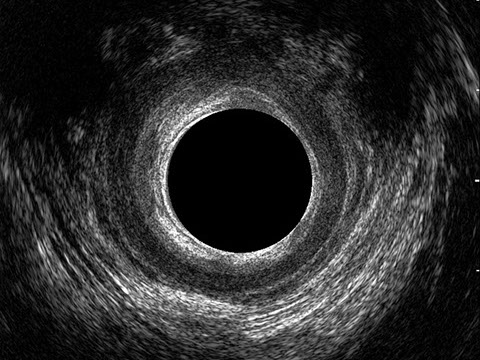

L’ecografia transanale è un esame diagnostico per immagini che consiste nell’introduzione di un trasduttore ad ultrasuoni. Le immagini qualitativamente migliori del canale anale sono ottenute usando un trasduttore rotante, montato in un manipolo rigido, che fornisce un’immagine a 360°. Con le apparecchiature più moderne è anche possibile ottenere immagini tridimensionali.

L’ecografia transanale permette di distinguere la sottomucosa che riveste il canale anale, lo sfintere anale interno, e lo sfintere anale esterno.

Le principali indicazioni all’esecuzione di tale esame sono lo studio dell’integrità delle strutture muscolari nei casi di incontinenza fecale, lo studio topografico dei processi settici perianali (ascessi e fistole) e lo studio dei processi proliferativi epiteliali (carcinoma anale).